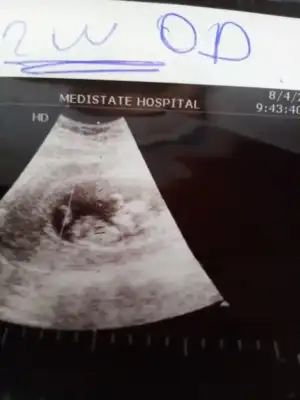

Erkek gibi olursa 13 hafta USG tekrar paylaşın USG net değil emin olamadimMerhaba. 11+5 teyim. Yorumlar mısınız![]()

Sağol canım inşallah haftaya baska doktora da gideceğim ama iki doktor kız dedi artık ücüncü de desin diye bekliyorum. Hayırlısı olsun allah olmayanlara da versin, oyladım canım

Kaç haftalık USG 11 12 13 hafta olmalı sanki kız gibi emin olamadım başka USG de paylasin12. Hafta ultrasonumuz bize de bakarmisin